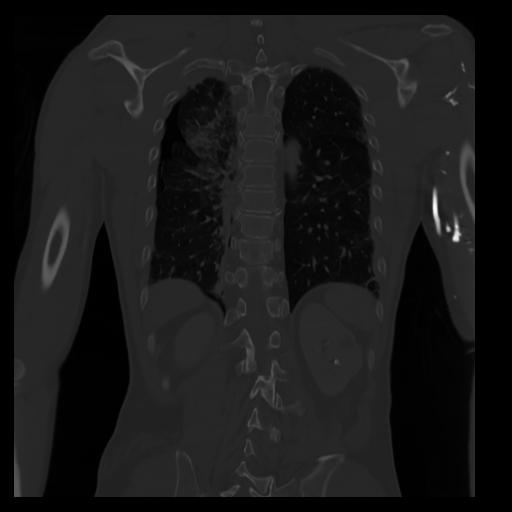

29 CUERPO,CE,Coronal,3.000,CUERPO,Coronal,